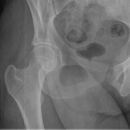

Hüftgelenk a.p.

Indikation

Cave: selten isoliert, meißt mit Luxation oder Azetabulum# kombiniert), Hüftgelenksluxation

Beurteilungskriterien

- CCD- Winkel (120-130°) Spongiosaarchitektur, Trajektorienverlauf im Schenkelhals (Cave: Bei nicht dislozierten SHF Diskontinuität der Trabekel oft einziges Frakturzeichen!)

- Shenton´sche Linie (Harmonischer Bogen aus kaudaler Schenkelhalskontur und der kranialen Zirkumferenz des For. obturatum)

- Gelenkstellung, Gelenkspaltweite (4-5mm nach medial, 3-4mm nach kranial), Luxation => Hüftkopf in ap und axialer Aufnahme in Azetabulum zentriert? Hüftkopfrundung?

- Azetabulumfraktur: vorderer und hinterer Pfannenrand, Pfannendachkontur, Köhlersche Tränenfigur, ggf. Zusatzaufnahmen (Ala- und Obturatoraufnahme), sowie CT

- medialer Azetabulumdachbogen (45° von der Hüftkopfmitte ausgehend nach vorne (!); Teil der lasttragenden Zone des Azetabulums, vgl. Obturatoraufnahme)

- Trochanter major et minor (Abriss, pertrochantäre #?)

- Weichteilzeichen (Fettstreifen medial des M.gluteus minimus zw. M.glutaeus minimus und medius, medial des M.iliopsoas; Konturschatten des M.obturatorius int.)

- med. Schenkelhalsfrakturen nach Pauwels I-III und nach Garden I-IV (2)

- SHF und Pertrochantere Frakturen AO-Klassifikation

- Lokalisation mediale, laterale, pertrochantäre und subtrochantäre Schenkelhalsfraktur

- Hüftgelenksluxation

- Hüftkopffrakturen nach Pipkin

- Einteilung der medialen Schenkelhalsfrakturen nach Pauwels:

Pauwels I°: Winkel zwischen Horizontalen und Frakturlinie < 30°

Pauwels II°: zwischen 30° – 70°

Pauwels III° : > 70°